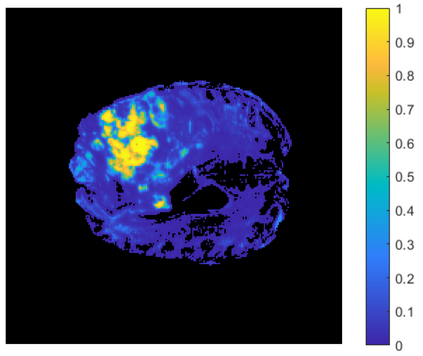

Gliomas are brain tumors composed of different highly heterogeneous histological subregions. Image analysis techniques to identify relevant tumor substructures have high potential for improving patient diagnosis, treatment and prognosis. However, due to the high heterogeneity of gliomas, the segmentation task is currently a major challenge in the field of medical image analysis. In the present work, the database of the Brain Tumor Segmentation (BraTS) Challenge 2018, composed of multimodal MRI scans of gliomas, was studied. A segmentation methodology based on the design and application of convolutional neural networks (CNNs) combined with original post-processing techniques with low computational demand was proposed. The post-processing techniques were the main responsible for the results obtained in the segmentations. The segmented regions were the whole tumor, the tumor core, and the enhancing tumor core, obtaining averaged Dice coefficients equal to 0.8934, 0.8376, and 0.8113, respectively. These results reached the state of the art in glioma segmentation determined by the winners of the challenge.